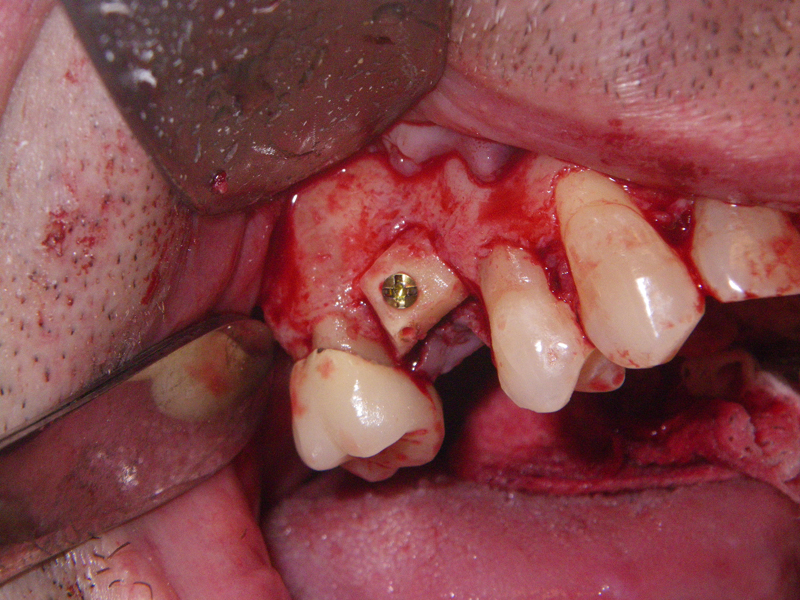

- Alveolar Ridge Augmentation

- Bone grafting – autogeneous, alogenic, xenogenic

- Blockgraft

- Incision

- Identify, don’t ‘skeletonize,’ mental nerves

- Midline, lateral score marks

- Osteotomy 5 mm below tooth apices & mental nerve

- Angulation of cut (Depends on planned movement)

- Downfracture (release ‘wings’)

- Fixation (plate, screws, wire)

- Layered closure (mentalis)